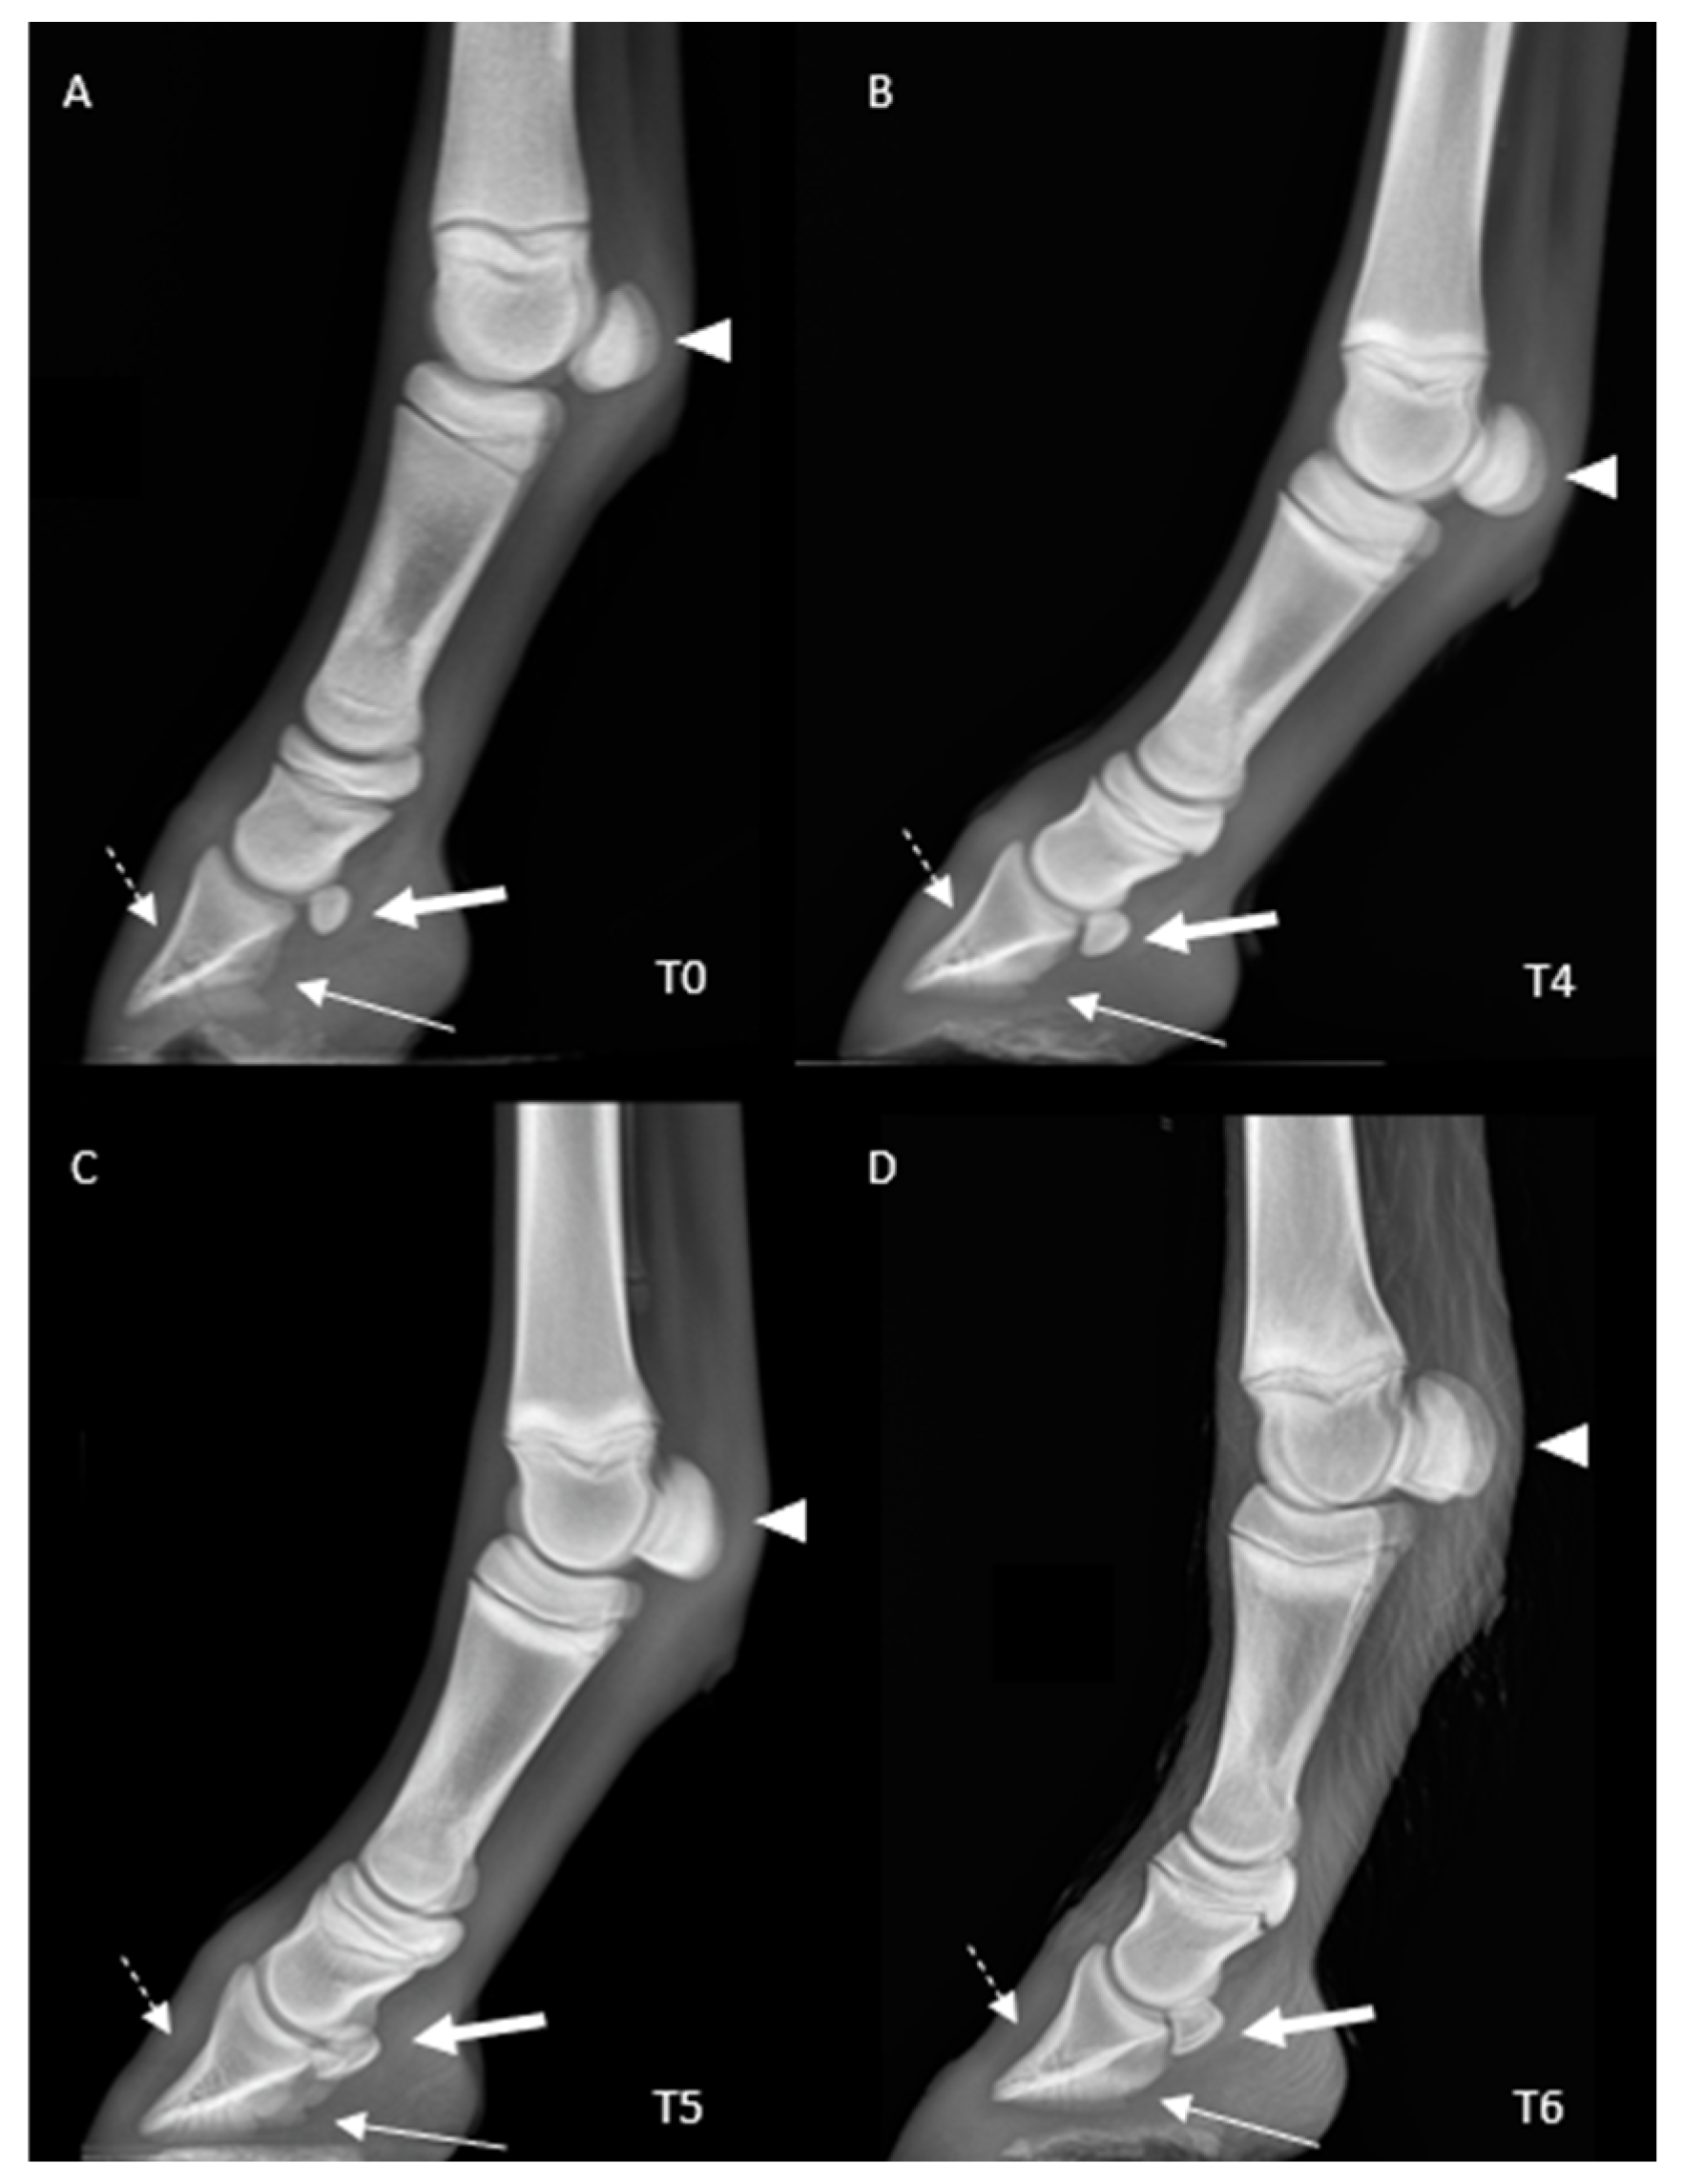

2.3. Radiological Parameters